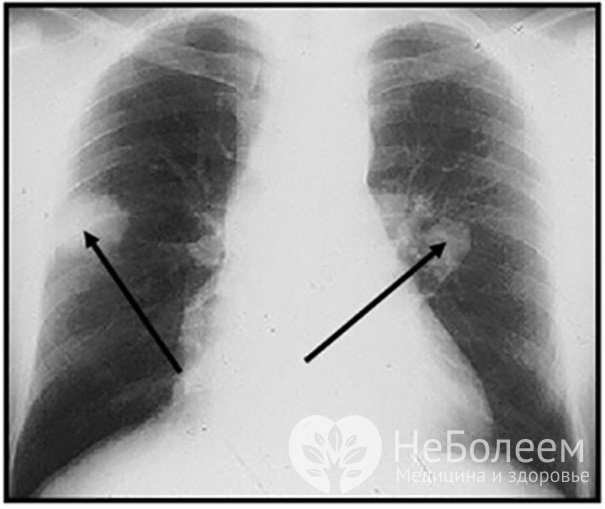

Рентгенография легких – легочные узлы при гранулематозе ВегенераПри необходимости в диагностике гранулематоза Вегенера используют и другие методы: например, компьютерную томографию или биопсию тканей верхних дыхательных путей с последующим гистологическим анализом.

Симптомы гранулематоза ВегенераУ 2/3 пациентов заболевание сопровождается образованием в легких деструктивных полостей, упорным кашлем, кровохарканьем.